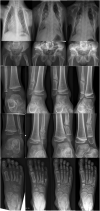

Parathyroid hormone-like hormone (PTHLH) plays an important role in bone formation. Several skeletal dysplasias have been described that are associated with disruption of PTHLH functioning. Here we report on a new patient with a 898 Kb duplication on chromosome 12p11.22 including the PTHLH gene. The boy has multiple skeletal abnormalities including chondrodysplasia, lesions radiographically resembling enchondromas and posterior rib deformities leading to a severe chest deformity. Severe pulmonary symptoms were thought to be caused by limited mobility and secondary sputum evacuation problems due to the chest deformity. Imaging studies during follow-up revealed progression of the number of skeletal lesions over time. This case extends the phenotypic spectrum associated with copy number variation of PTHLH.